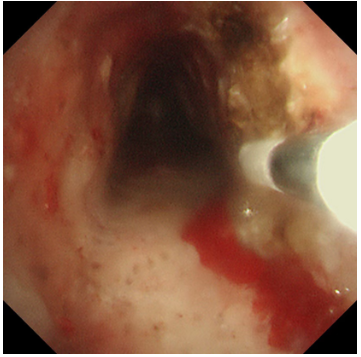

冷冻修复,深度“清创”:随后,应用冷冻探头对残余的增生组织及基底进行冻融治疗。极低温的探头接触组织,能使其变性、坏死并最终脱落,同时还能有效止血、减少瘢痕形成。这一步骤如同为气道进行一次深度的“保养与清洁”,能更彻底地清除病灶,降低复发风险。